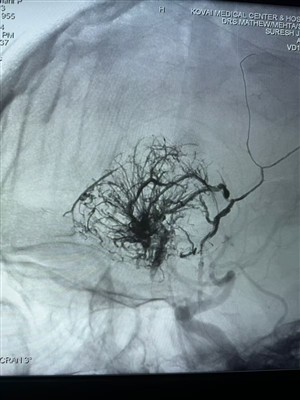

První případ hypervaskulárního nádoru hlášený v IndiiS radostí sdílím tento první případ hypervaskulárního nádoru provedený v Indii. Byl ošetřen pomocí Lava Liquid Embolic System od NeuroSafe Medical Co., Ltd.. Díky Dr. Mathew Cherian. Byl průkopníke...